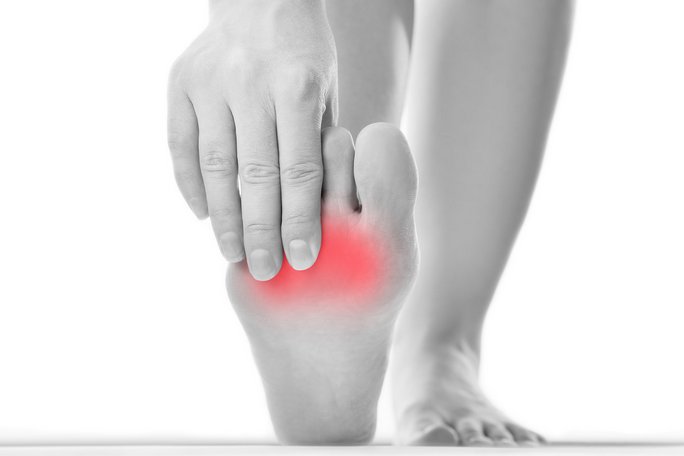

Если воспалился сустав на ноге, то заметить это возможно по внешнему показателю. Значительно меняется внешний вид сустава нижней конечности. Пораженное соединение отечное, горячее на ощупь, кожный покров имеет блеск, покрасневшее.

- отек;

- боль;

- покраснение локализованного места;